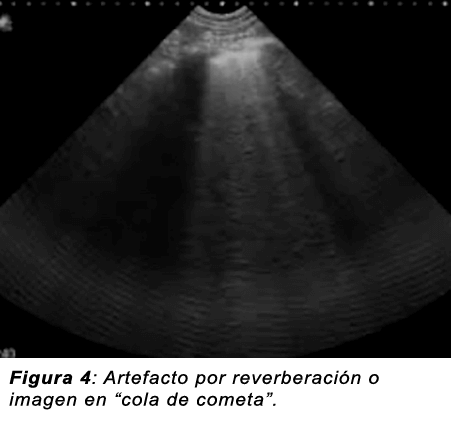

Reverberación o imagen en “cola de cometa”: Se produce por la progresión del haz ultrasónico a través de interfaces muy reflectantes como puede ser el metal o el cristal y disminuyen progresivamente de intensidad con la distancia.